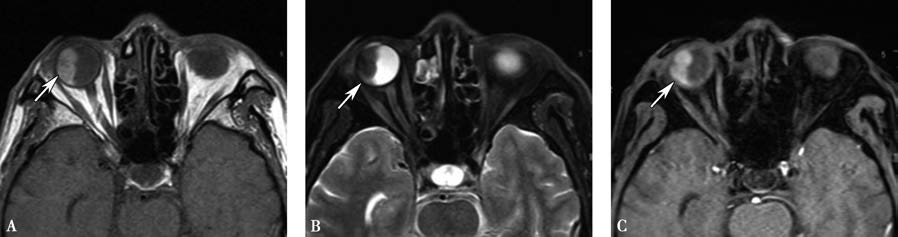

Classic UM appears as a hyperintense signal on T1-weighted imaging and a hypointense signal on T2-weighted imaging, with significant enhancement on post-contrast scans. MRI also provides valuable information regarding possible extrascleral extension of the tumor.

Figure 3 MRI of uveal melanoma

A. T1WI shows an elliptical intraocular mass in the right eye with high signal intensity.

B. T2WI shows the intraocular mass as hypointense.

C. Post-contrast imaging reveals the intraocular lesion with irregular enhancement in the right eye.